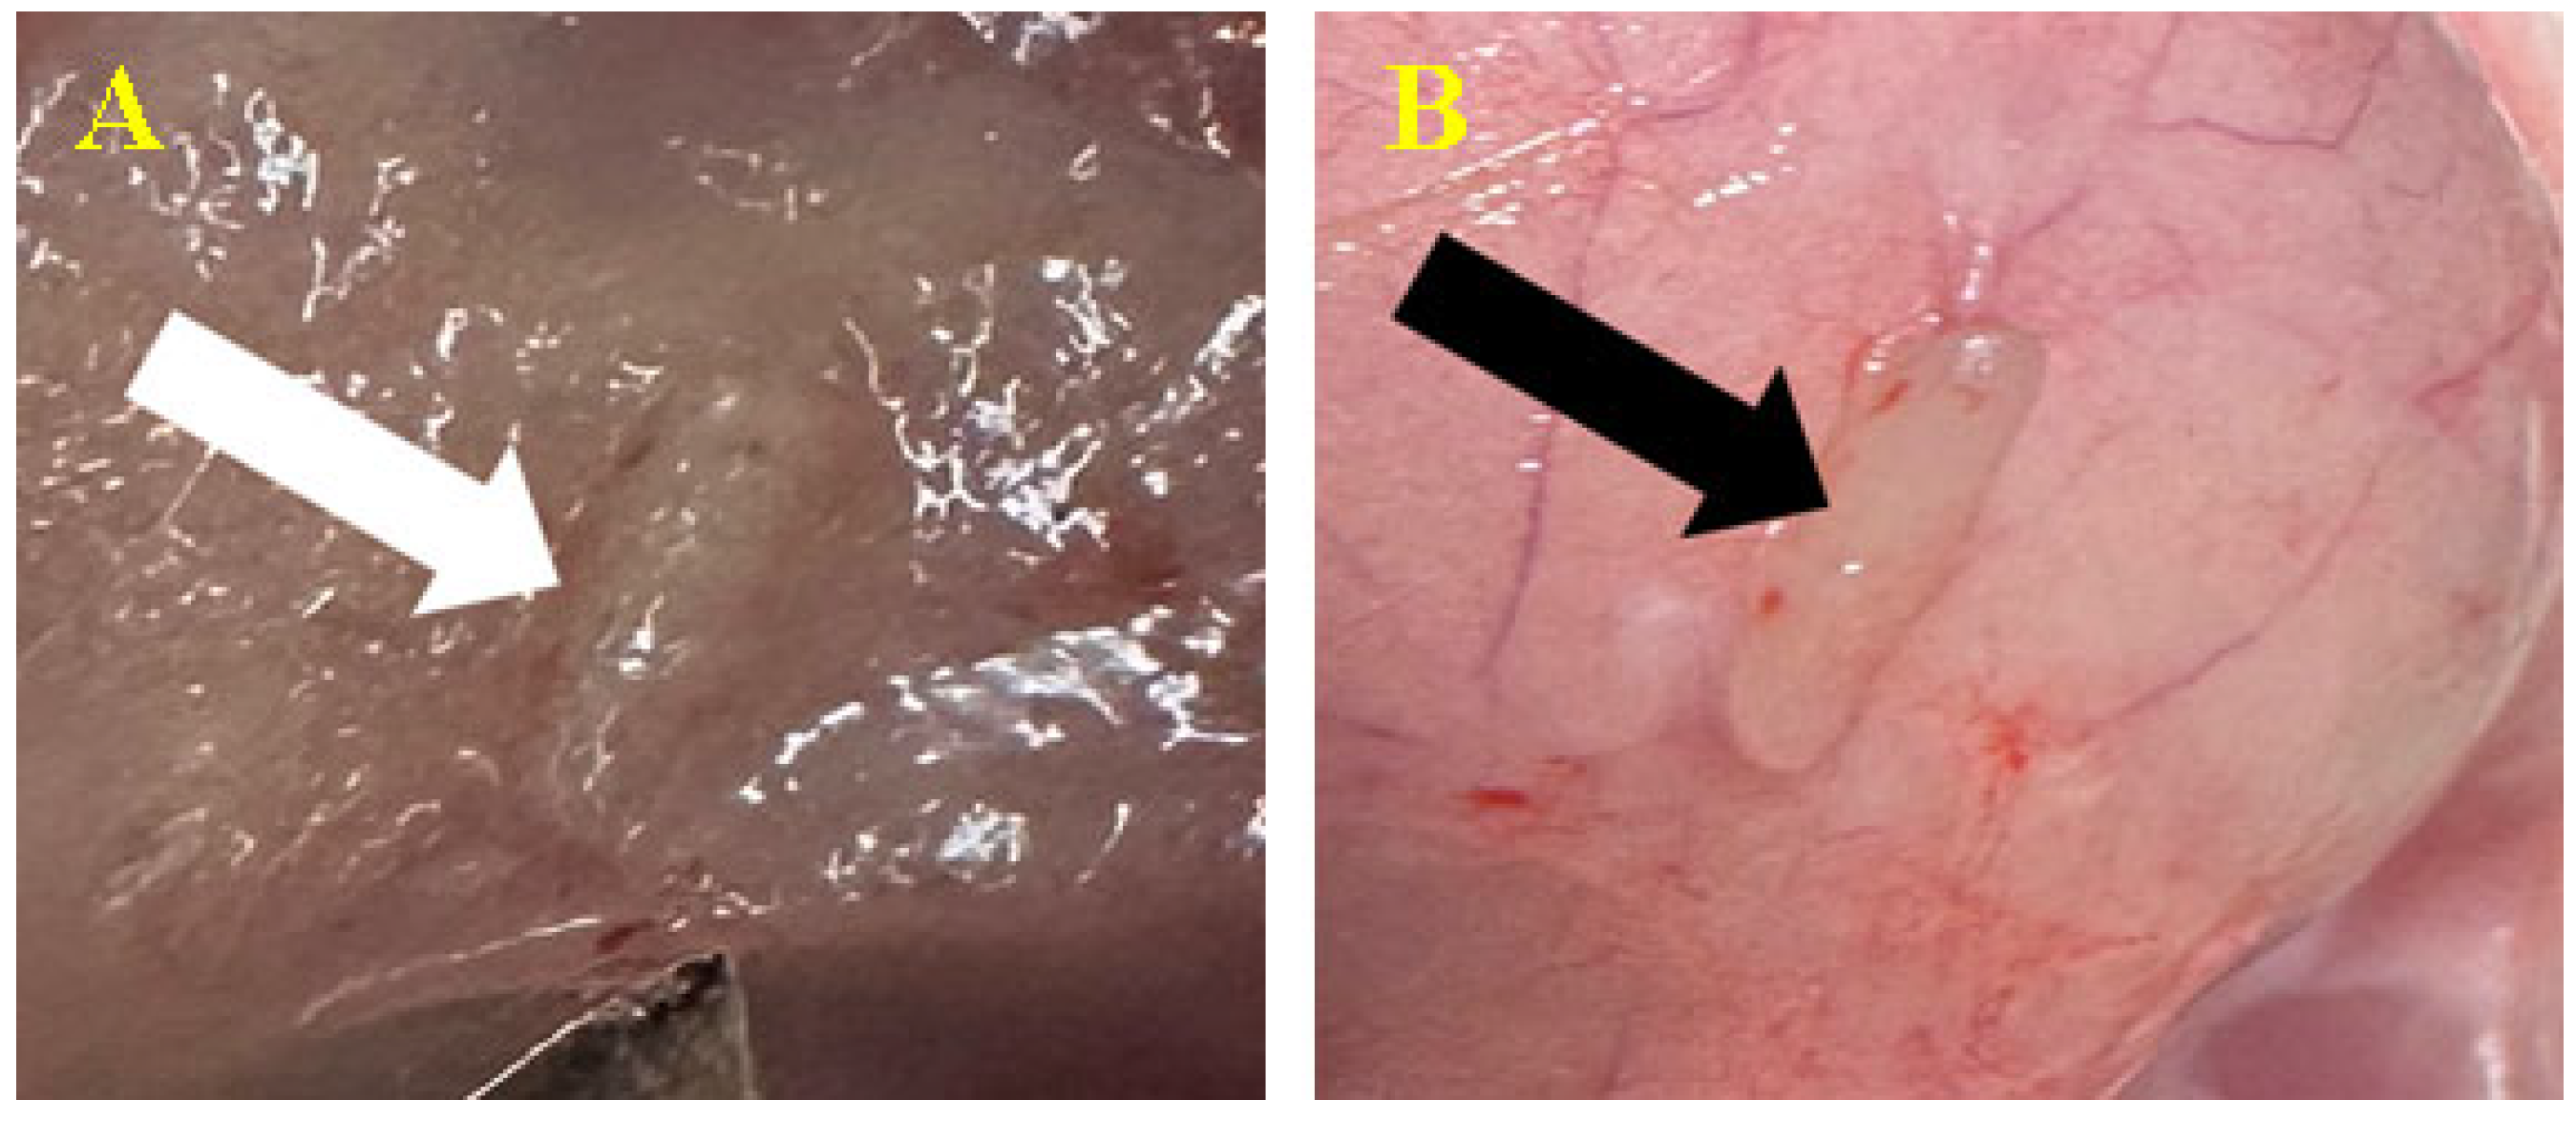

3.3.1. Subcutaneous

3.3.2. Peri/Intramuscular